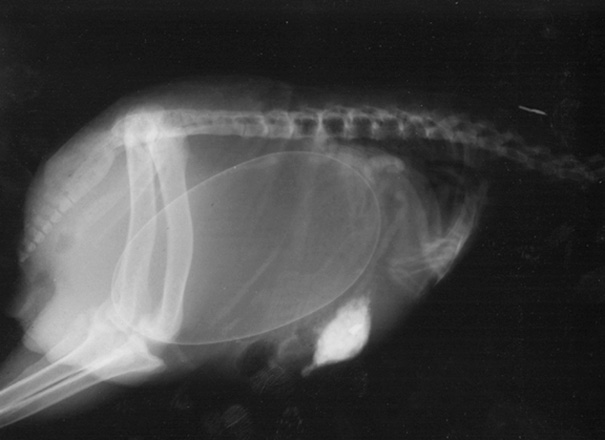

A Pregnant Kiwi

There eggs are absolutely gigantic for the size that they are. How they don't rip apart laying something like a third there size is amazing to say the least. Google kiwi with egg.

This isn't pregnancy. I get what the post is getting at but anything that lays eggs doesn't experience "pregnancy"